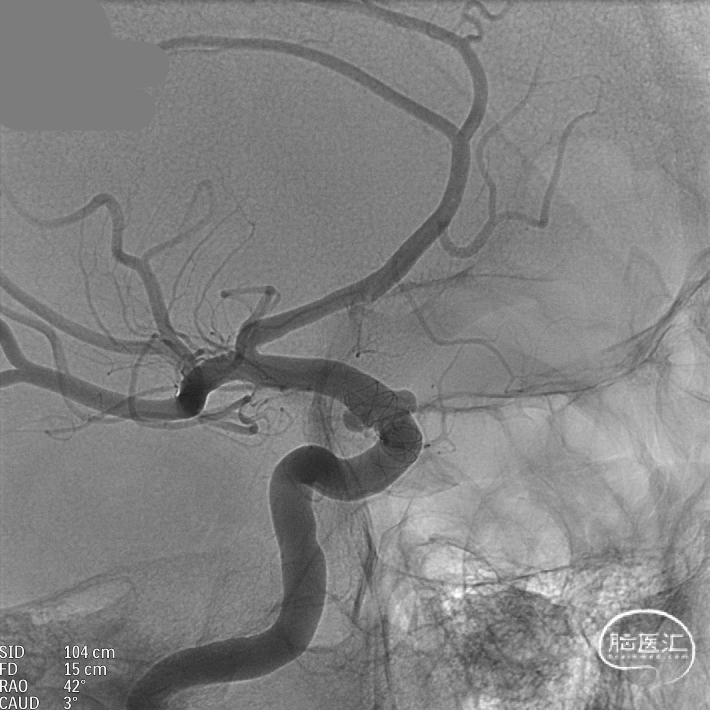

支架到位,远端打开(正侧位):4.75-20mm支架在大脑中动脉M1段打开,回撤至C6段远端锚定。支架释放过程中,轻柔推送支架系统,可见支架导管沿血管壁大弯侧走行,支架打开良好。

支架中段打开:

输送导丝及微导管回撤:释放至支架末端,减张系统,回撤支架导管,释放支架。沿支架推送杆,调节系统张力,将支架导管通过支架到达C7段。

支架内使用成襻微导丝进行按摩,使支架充分贴壁。

术后造影:支架覆盖两枚动脉瘤瘤颈,贴壁良好,瘤体内可见造影剂滞留。

术后支架显影:

支架到位,原位释放,前段打开。

造影确认支架远端打开充分,贴壁良好,继续推送支架。

支架全部释放,调整张力,微导管通过支架,回收输送导丝。

术后造影:支架充分覆盖动脉瘤瘤颈,贴壁良好,瘤体内可见造影剂滞留。

术后支架显影:定位精准,未覆盖颞前动脉及大脑前动脉。